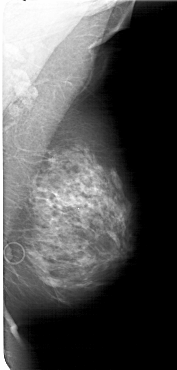

A_1632_1.LEFT_MLO

LEFT_MLO LINES 6316 PIXELS_PER_LINE 3226 BITS_PER_PIXEL 12 RESOLUTION 43.5 OVERLAY